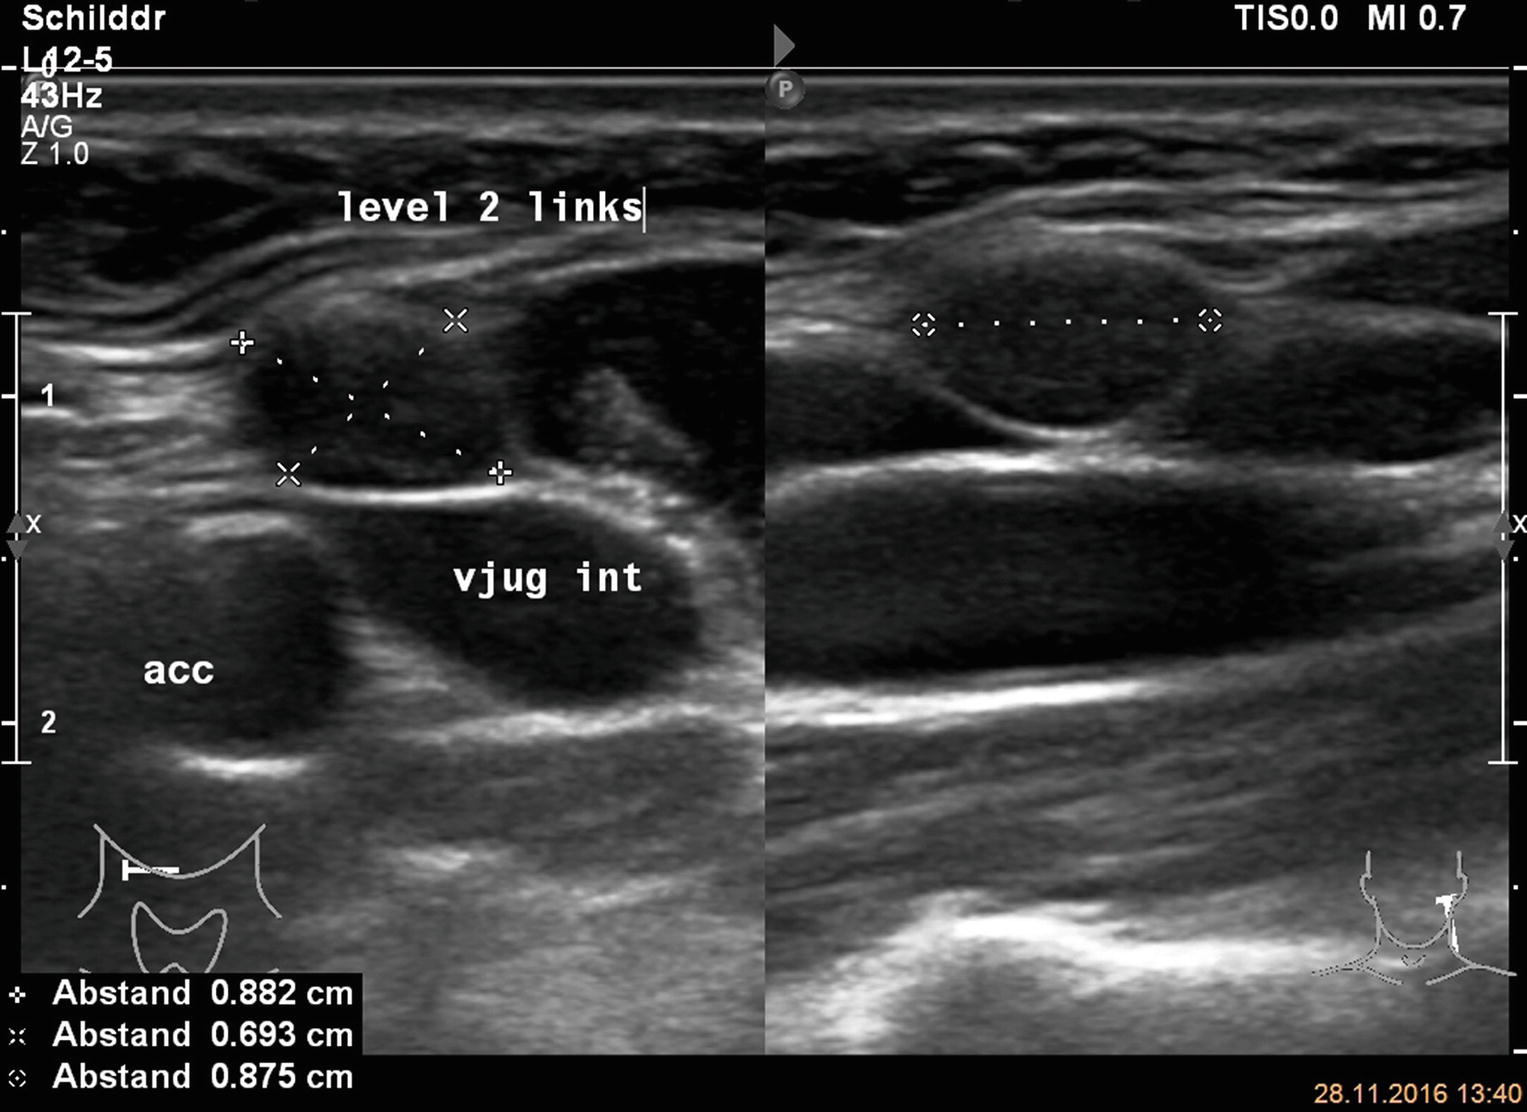

The person operating the ultrasound will sweep, or fan, the probe back and forth to look at different areas in 90 degree angle images. In addition, the following tests may be used to diagnose head and neck cancer: Cancerous lymph nodes can occur anywhere on the neck and are typically described as firm, painless, and sometimes may be immovable. In the normal neck, about 90% of nodes with a maximum transverse diameter greater than 5 mm will demonstrate an echogenic hilus on high resolution ultrasound. Symptoms of head and neck cancer can include:

Air and bone also reflect sound waves. A lump in the neck —cancers that begin in the head or neck usually spread to lymph nodes in the neck before they spread elsewhere. A neck ultrasound may help diagnose (find): Breast ultrasound images are seen from superficial (skin) to deep (chest wall muscle) over a segment of tissue. A neck ultrasound can be used to observe the thyroid gland to look for nodules, growths, or tumors. But now i am worried that the reason the lump didn't show on the ultrasound is because it is actually under the skin in my neck (i.e in my throat) rather than on my actual thyroid/neck. David dang answered 14 years experience radiology node, cyst or others: A small lump on the neck usually is a lymph node, a small sebaceous cyst or a lipoma, although it could be something else. The most common symptom of thyroid cancer is a hard lump on the neck—but most patients experience no symptoms at all. This means that they are larger than about 1 centimeter (about 1/2 inch) across. Optimal positioning and exposure of the neck for ultrasound of the thyroid and parathyroid glands (a, b) and lateral neck for lymph node examination and mapping (c).while the vast majority of patients are supine on the exam table with a pillow supporting the shoulders to allow gentle neck extension, keep in mind that some patients have beautiful anatomy (d) that allows ultrasound exam even in. 1), and the presence of an echogenic hilus within lymph nodes was previously considered a sign of benignity. What does a healthy kidney look like on an ultrasound?

A small device called a transducer is moved over the area. Optimal positioning and exposure of the neck for ultrasound of the thyroid and parathyroid glands (a, b) and lateral neck for lymph node examination and mapping (c).while the vast majority of patients are supine on the exam table with a pillow supporting the shoulders to allow gentle neck extension, keep in mind that some patients have beautiful anatomy (d) that allows ultrasound exam even in. The camera remains attached either to a flexible tube called endoscope or to a probe, while it passes within an opening in your body, often your mouth. In the normal neck, about 90% of nodes with a maximum transverse diameter greater than 5 mm will demonstrate an echogenic hilus on high resolution ultrasound. Ultrasound an ultrasound is sometimes used, especially to look at the thyroid, salivary glands and lymph glands in the neck. A neck lump or nodule is the most common symptom of thyroid cancer. Should your doctor suggest that you undergo a neck ultrasound, you can be confident that your scan will be conducted by highly trained, experienced and caring sonographers. But now i am worried that the reason the lump didn't show on the ultrasound is because it is actually under the skin in my neck (i.e in my throat) rather than on my actual thyroid/neck.

If a biopsy is needed, doctors use ultrasound to scan the area again, ensuring that they know exactly where to place the needle. In addition, the following tests may be used to diagnose head and neck cancer: And my neck look like an old shapai. A lump will form when a cancer cell infiltrates the capsule and multiplies. These are frequently seen in nodules containing papillary thyroid cancer. But ultrasound is usually the first choice for looking at the thyroid and neck structures. The normal neck contains scores of lymph nodes some of which are easily seen with ultrasound. Ultrasound an ultrasound is sometimes used, especially to look at the thyroid, salivary glands and lymph glands in the neck.